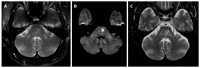

We describe common and less common diseases that can cause magnetic resonance signal abnormalities of middle cerebellar peduncles (MCP), offering a systematic approach correlating imaging findings with clinical clues and pathologic mechanisms. Myelin abnormalities, different types of edema or neurodegenerative processes, can cause areas of abnormal T2 signal, variable enhancement, and patterns of diffusivity of MCP. Pathologies such as demyelinating disorders or certain neurodegenerative entities (e.g., multiple system atrophy or fragile X-associated tremor-ataxia syndrome) appear to have predilection for MCP. Careful evaluation of concomitant imaging findings in the brain or brainstem; and focused correlation with key clinical findings such as immunosuppression for progressive multifocal leukoencephalopahty; hypertension, post-transplant status or high dose chemotherapy for posterior reversible encephalopathy; electrolyte disorders for myelinolysis or suspected toxic-drug related encephalopathy; would yield an appropriate and accurate differential diagnosis in the majority of cases.